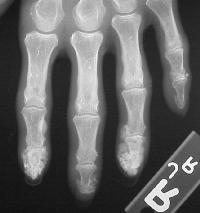

Tightness of skin is apparent over the dorsal fingers, with loss of extensor skin creases.

The right index and middle fingertips are large, hard and tender.